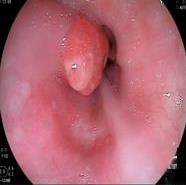

• 内镜诊断和治疗十二指肠黏膜下恒径动脉破裂出血并活动性出血的价值(附6例报告)

2026, 32(1):80-83. DOI: 10.12235/E20250357

摘要:目的 探讨内镜诊断和治疗十二指肠黏膜下恒径动脉破裂出血并活动性出血的价值。方法 回顾性分析2015年6月-2023年1月该院经内镜确诊十二指肠黏膜下恒径动脉破裂出血并活动性出血的6例患者的临床资料。总结临床表现、内镜下特征和治疗转归。结果 于24 h内完成急诊内镜检查,证实6例均为单纯十二指肠黏膜下恒径动脉破裂出血,并成功行内镜下钛夹止血治疗。结论 内镜诊断十二指肠黏膜下恒径动脉破裂出血所致的大出血,具有较高的价值。此外,于内镜下及时采取积极、有效的干预措施,可快速止血,降低死亡率。值得应用于临床。